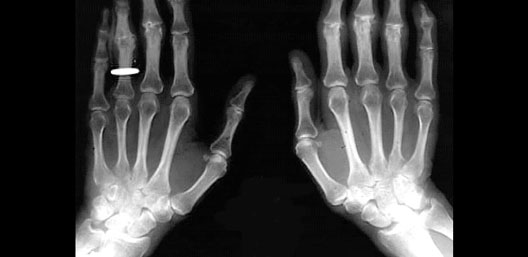

X-Ray of Hands

Roll mouse over image to display labels.

1. Ulna

2. Styloid process of ulna

3. Radius

4. Wrist Bones

5. 5th metacarpal bone

6. 1st metacarpal bone

7. Sesamoid bone

8. 1st proximal phalynx

9. 1st distal phalynx

10. 5th proximal phalynx

11. 5th middle phalynx

12. 5th distal phalynx